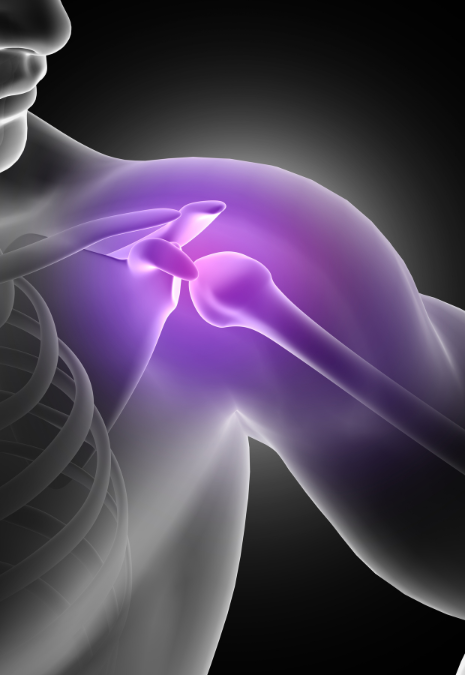

- Shouldercare

- Shouldercare

- Shouldercare

- Shouldercare

- Shouldercare